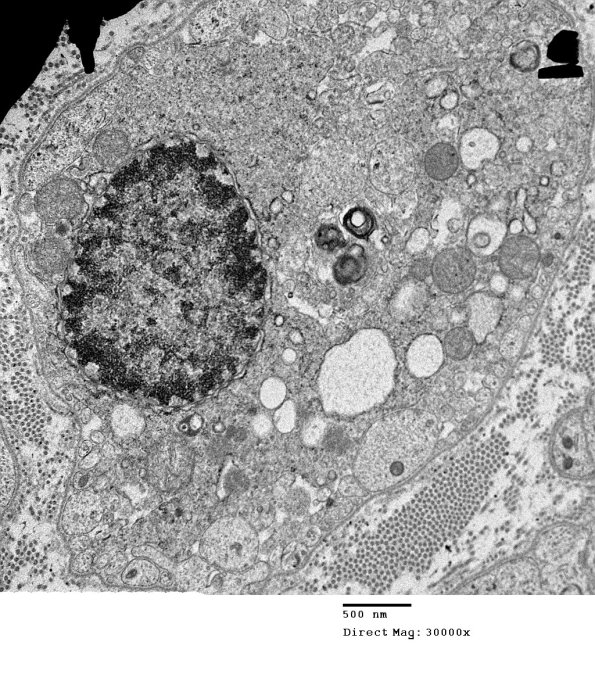

Much of the fascicle looked very axon depopulated with some residual debris and a few ongoing degenerating axons. (electron micrograph)